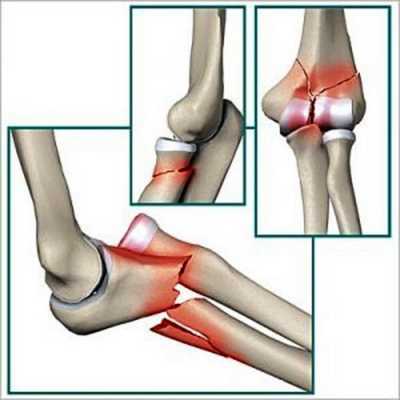

Переломы нижних отделов плечевых костей

При установлении внутрисуставного перелома прогноз на полное выздоровление хуже. Задачами терапии становится качественное совмещение отломков и восстановление хрящевых поверхностей. Чаще всего диагностируются следующие травмы:

- травмы чрезмыщелковые, межмыщелковые. Это самые часто диагностируемые виды переломов, обычно возникающие при сильном ударе в локоть. Поддерживающие надмыщелки костные структуры разрушаются, что становится причиной изменения соотношения костей. Для таких травм характерно серьезное повреждение хрящевых тканей, восстановление которых является сложной задачей. После репозиции суставных элементов они крепятся винтами и пластинами до полного их сращения. Это не станет ограничением для постепенной разработки сустава.